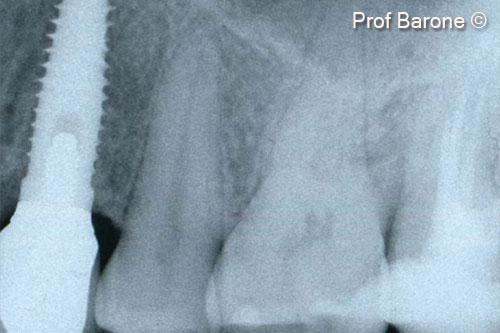

Một bệnh nhân nữ (27 tuổi) có biểu hiện nhiễm trùng cấp tính và mủ từ lỗ rò ở miệng.